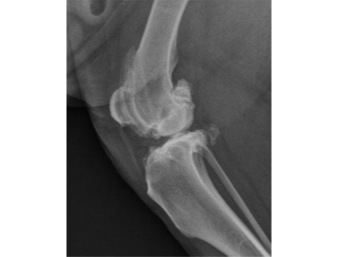

Figure 2. Radiograph of a canine stifle (knee joint) with advanced arthritis. Same dog as in figure 1, opposite stifle.